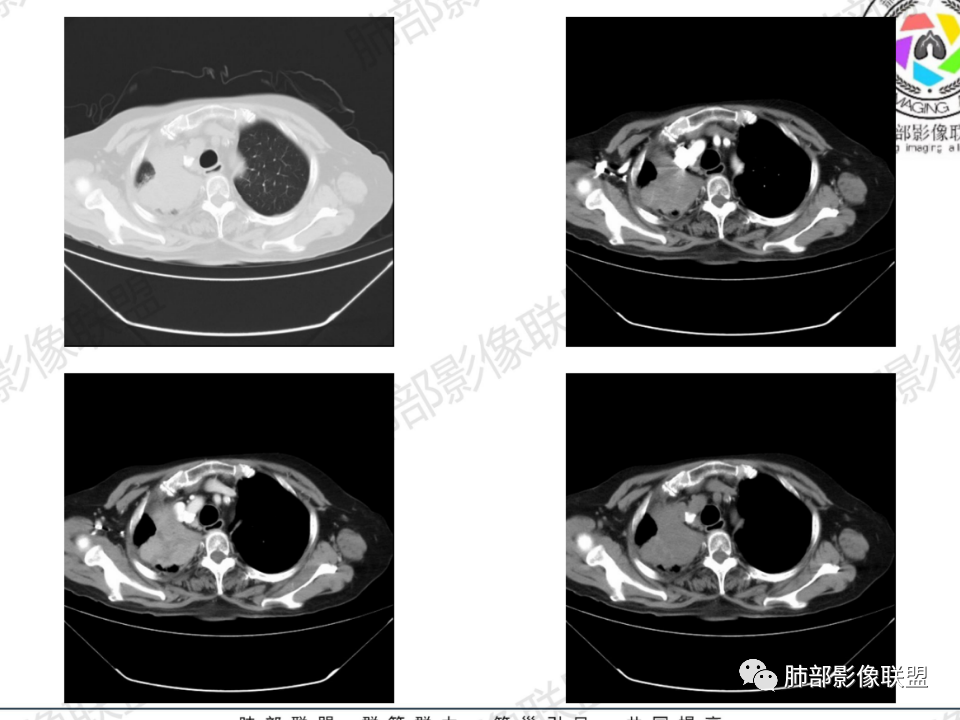

右肺体积小,提示既往结核

支气管影

前,后段都在,没有堵塞

支气管壁增厚,周围磨玻璃边界不清,提示炎症。胸膜下钙化符合结核

这个层面往上应该是尖段,显示不清

背段支气管周围增厚伴钙化,符合结核改变

结核是肯定有。现在最大问题是尖段

近端显示不清,但是远端是粘液栓,可以认为是还行的

如果是近端鳞癌,远端应该会堵塞,不会整个肿块里面还有较为通畅的支气管

这个区域我们看到密度与周围一致,并不是肺癌伴周围不张的感觉,所以鳞癌暂时是不支持的

相应上叶尖端及前段支气管开口未能追踪(阻塞),开口处见钙化。病灶渐进性强化,并衬托出较完整尖段及前段含液支气管影。支气管开口区域未见异常高密度强化(如类癌等)及相对乏血供区(如鳞癌)。病灶区未见液化坏死。右上纵隔及胸廓入口区未见病灶胸膜外突破(栽赃)。